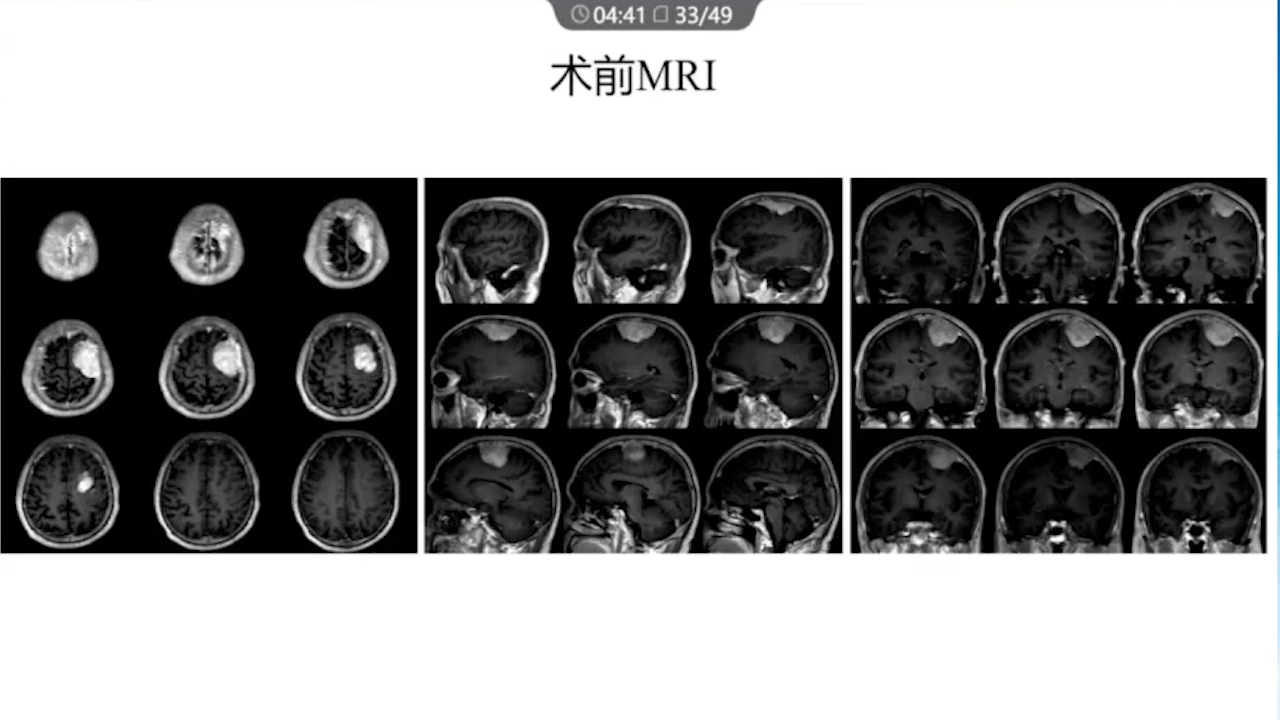

1、术前需要完善的影像学检查、多模态融合及神经导航以进行精确的肿瘤及静脉血管定位。